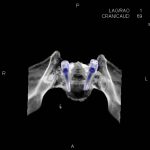

- Diagnosticul fracturilor:

- Unice

- Multiple

- Cu înfundare

- Complexe cranio-sinusale

- Complexe cranio-etmoidale

- Complexe cranio-orbitare

- Complexe cranio-faciale